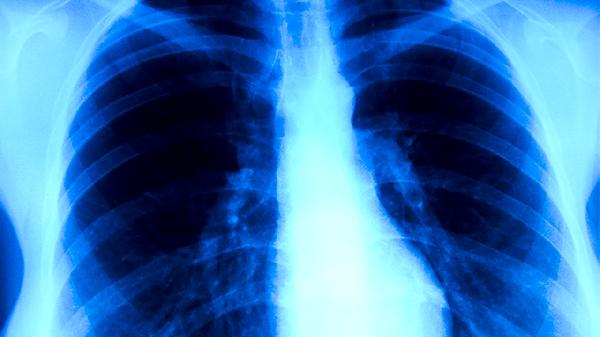

既往治疗不完整是复发的主要诱因。部分患者症状缓解后擅自停药,导致休眠期结核杆菌重新激活。糖尿病控制不佳会削弱巨噬细胞杀菌功能,增加复发风险。与活动性肺结核患者密切接触可能发生再感染。复发时常见低热、夜间盗汗、咯血等症状,CT可见原有病灶周围出现浸润影。药敏试验对调整治疗方案具有关键作用。

建议康复期患者每3-6个月进行胸部X线复查,保持均衡饮食补充优质蛋白和维生素A。避免过度劳累和熬夜,戒烟限酒以维持呼吸道防御功能。出现持续咳嗽伴体重下降应及时做痰涂片检查。密切接触者需进行结核菌素皮肤试验筛查。接种卡介苗可降低儿童重症发生率,但对成人预防复发作用有限。